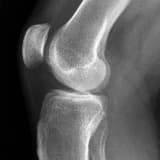

Menisküs Yırtıkları Vücudumuzun en sık yaralanan bölgelerden biriside menisküslerimizdir. Meniskü...